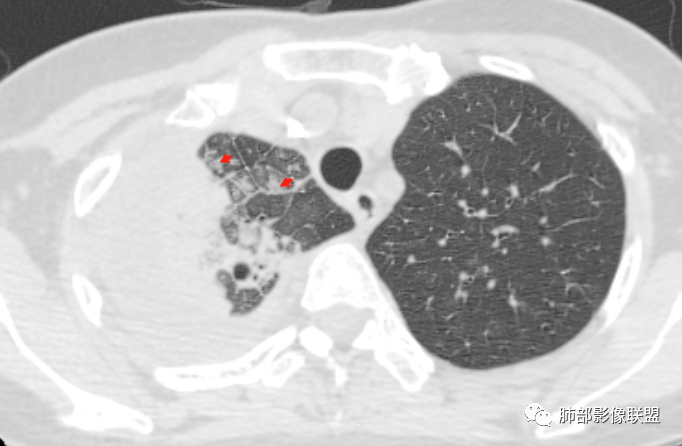

问个问题:这是啥?空洞?扩张支气管?

感觉像是扩张的支气管,不确定

这是扩张大支气管?还是囊腔?

空洞?

犹豫的点在于位置,与支气管关系。

一般空洞——应该在病灶的中央或实变区,这个在边缘。

囊腔?按理是近端支气管狭窄,导致气体潴留,不太符合。

因为大片实变支气管扩张原因:周围牵拉,支气管壁破坏。

这个在边缘,周围没有牵拉等因素,所以应该是壁的破坏。

壁破坏,这样的就需要观察整个壁的形态。

病灶本身占位效应,边缘膨隆,边缘没有收缩的迹象,也就是说支气管周围没有牵拉的因素导致其扩张,我们只能考虑支气管本身导致的扩张。

1、结核类的慢性炎症——狭窄、扩张、扭曲;

2、神经、肌肉破坏,导致支气管收缩不理想——光滑、通畅、远端扩张;这一类——淋巴瘤.

为啥不说急性炎症?急性炎症:边缘模糊,膨隆,一般属于渗出为主阶段,修复被渗出掩盖——占位效应明显,内部的支气管是受压狭窄的.

从支气管的改变:要警惕淋巴瘤。左肺病变沿支气管血管束分布,支持间质为主病变。